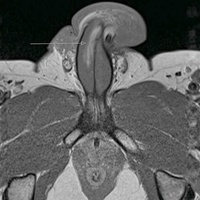

Повреждение уретры представляет собой частичное или полное нарушение ее целостности вследствие механического воздействия.